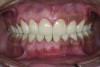

The final restorations were fabricated in the laboratory using monolithic lithium disilicate, and then tried-in in the patient’s mouth and verified for esthetics and function. They were then bonded with dual-cured resin cements following the same protocol as outlined for the anterior teeth.

The final restorations depicted restoration of form, function, and beauty, with good harmony of restoration and the periodontium (Figure 19 through Figure 25). MIP was in harmony with CR, and right and left lateral excursion discluded all posteriors with anterior group function. The postoperative orthopantomogram (OPG) (Figure 26) shows the treatment done while maintaining the vitality of anterior teeth.

Figure 20. Postoperative 1:2 retracted frontal view.

Figure 20